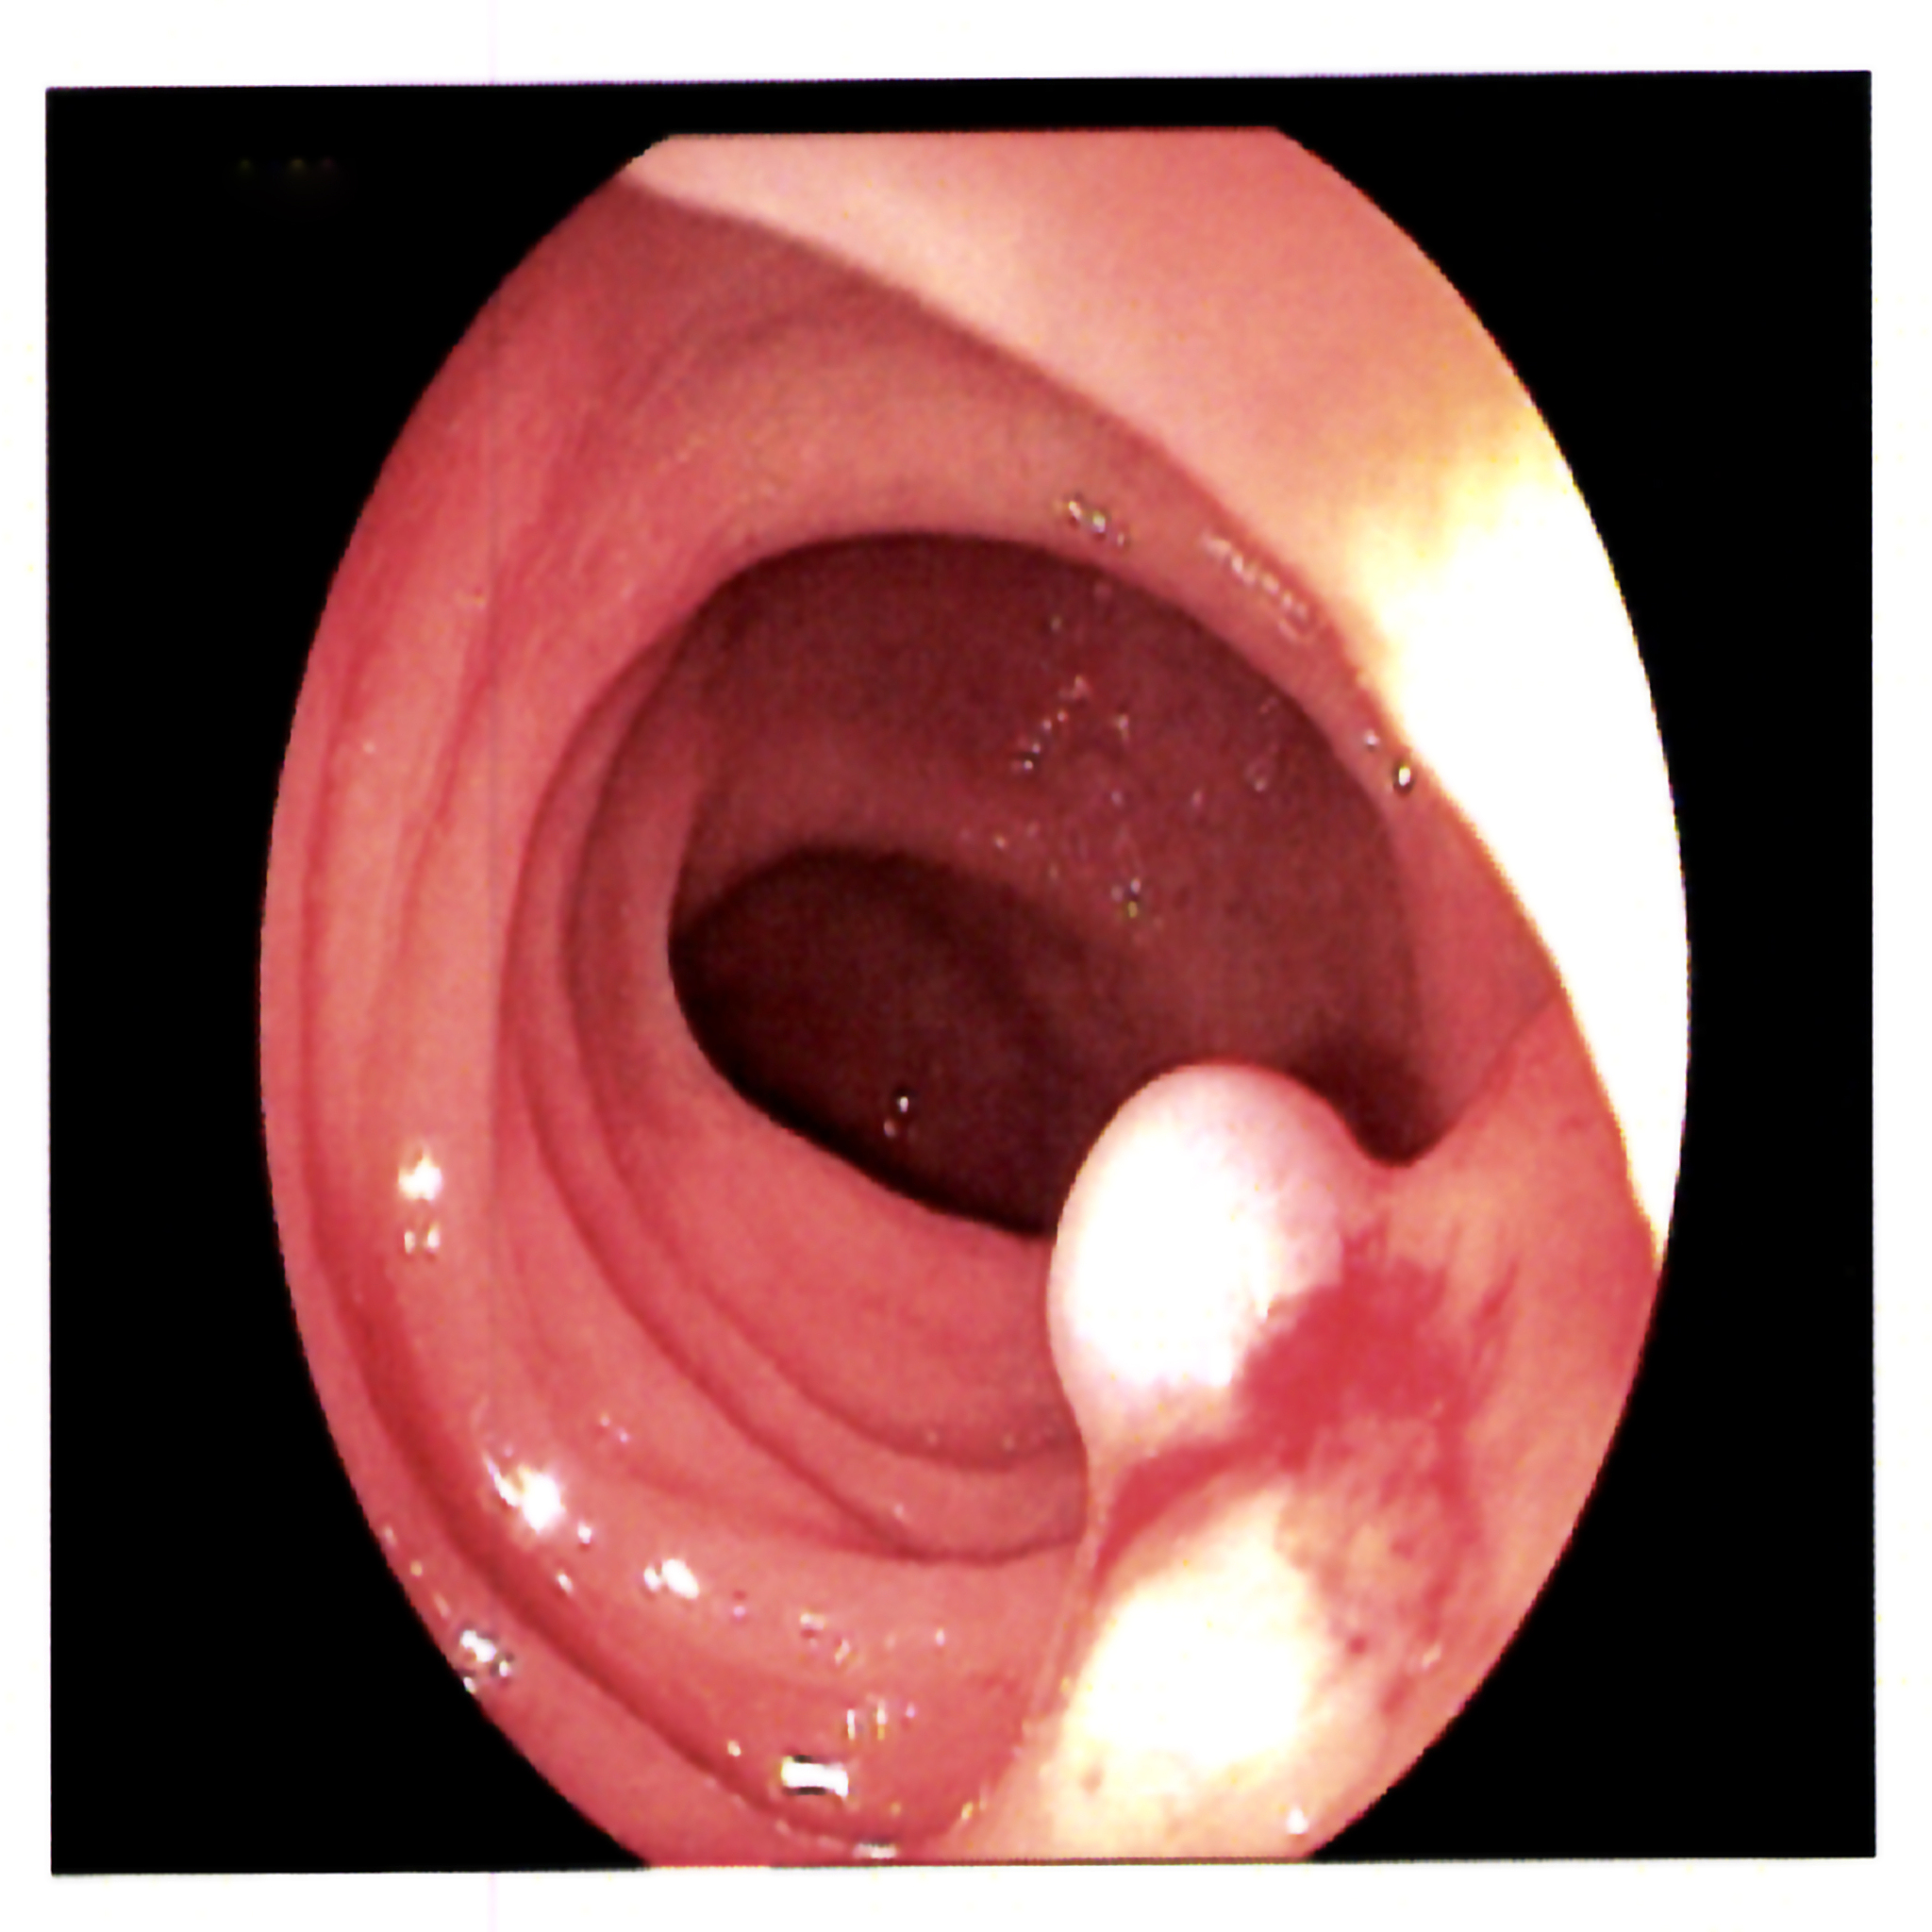

息肉是指人体某些部位的黏膜表面出现的一种肿块,通常呈现为突起的小结节。它们常见于鼻腔、喉咙、消化道、子宫颈等部位。息肉通常是良性的,但在一些情况下可能会转变为恶性肿瘤。息肉的具体原因尚不清楚,但与遗传因素、慢性炎症、感染、不良生活习惯等有关。一些常见的症状包括出血、疼痛、感觉异物、声音嘶哑等。治疗方法包括手术切除、电凝、冷冻疗法等。